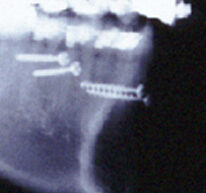

噛み合わせを見て頂きます。正面から撮影した状態です。

2分ほどで硬化する粘土のようなものを噛んで頂きました。噛んでいない事がこれでよくわかると思います。上下の歯が当たっているのは1か所だけでした。しかも1点です。歯列弓の幅がまったく合っていませんでした。これは大変お気の毒な状態でした。どこで物を食べればよいのでしょう。

横から見たところです。噛んでいません。この症例は歯を抜かずに矯正治療しています。診断は誤っています。現状は歯列が拡大してしまって出っ歯になっています。少なくとも上顎の小臼歯を抜歯してそのスペースを使って前歯を内側に移動し、歯列弓を小さく縮小する必要があります。おそらく以前の担当医はリンガルブラケットを使用して歯を抜いて治療する能力がなかったのでしょう。マウスピース型の装置でも非抜歯というのがよくあります。歯を削って口もとを後退させる。期待したほどの効果はありません。使用する装置の都合によって診断が変わって非抜歯になる事はありません。それはおかしいです。